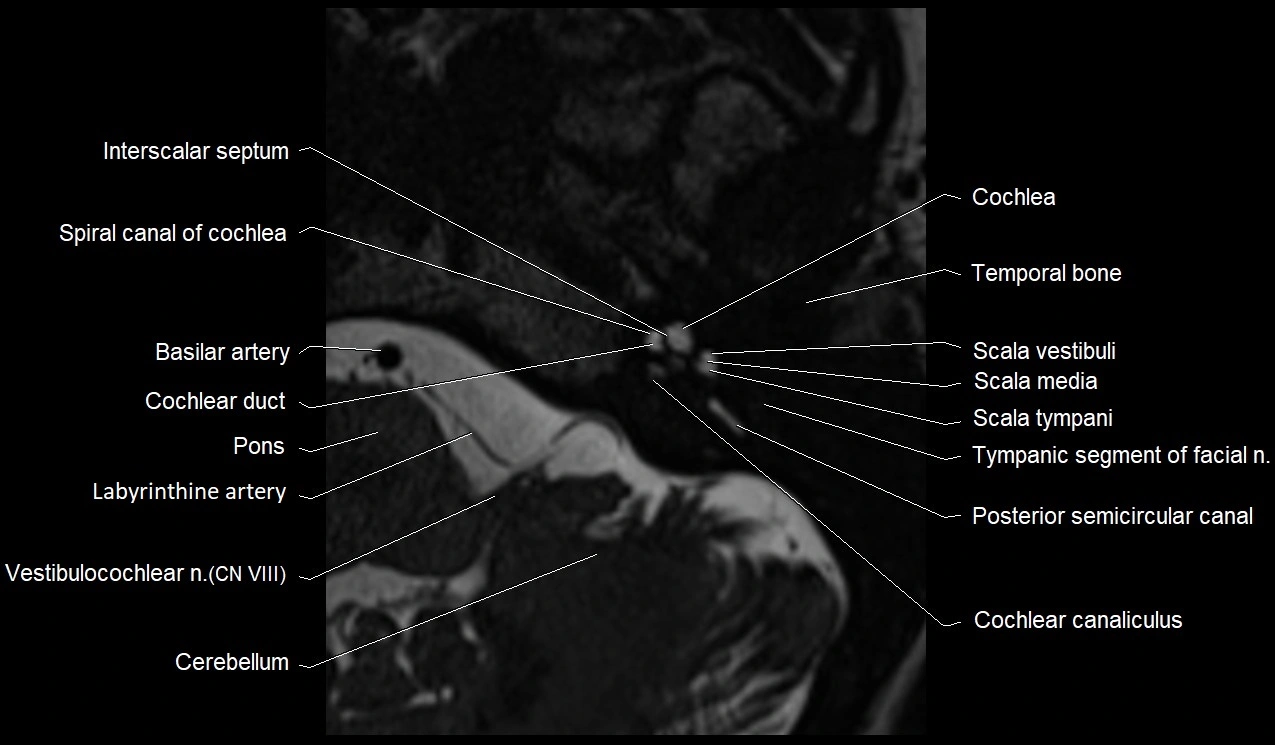

MRI images

image